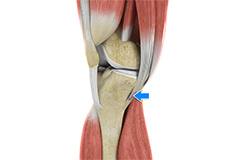

Anterior Knee Pain

Anterior knee pain is characterized by chronic pain over the front and center of the knee joint. It is common in athletes, active adolescents (especially girls) and overweight individuals. Anterior knee pain refers to various conditions, which include runner's knee or patellar tendinitis, and chondromalacia of the patella.